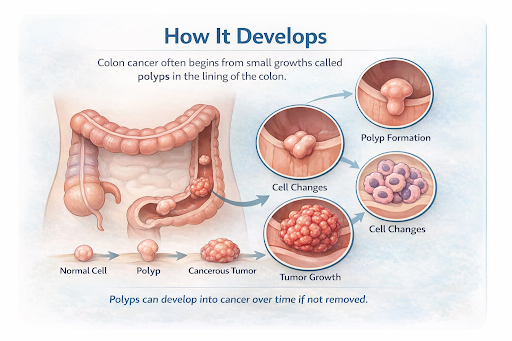

4. How It Develops

Colon cancer usually develops when normal cells in the lining of the colon undergo abnormal changes and begin to grow uncontrollably. These changes may start as polyps, which are small growths that can gradually become cancerous over time if not detected and removed.